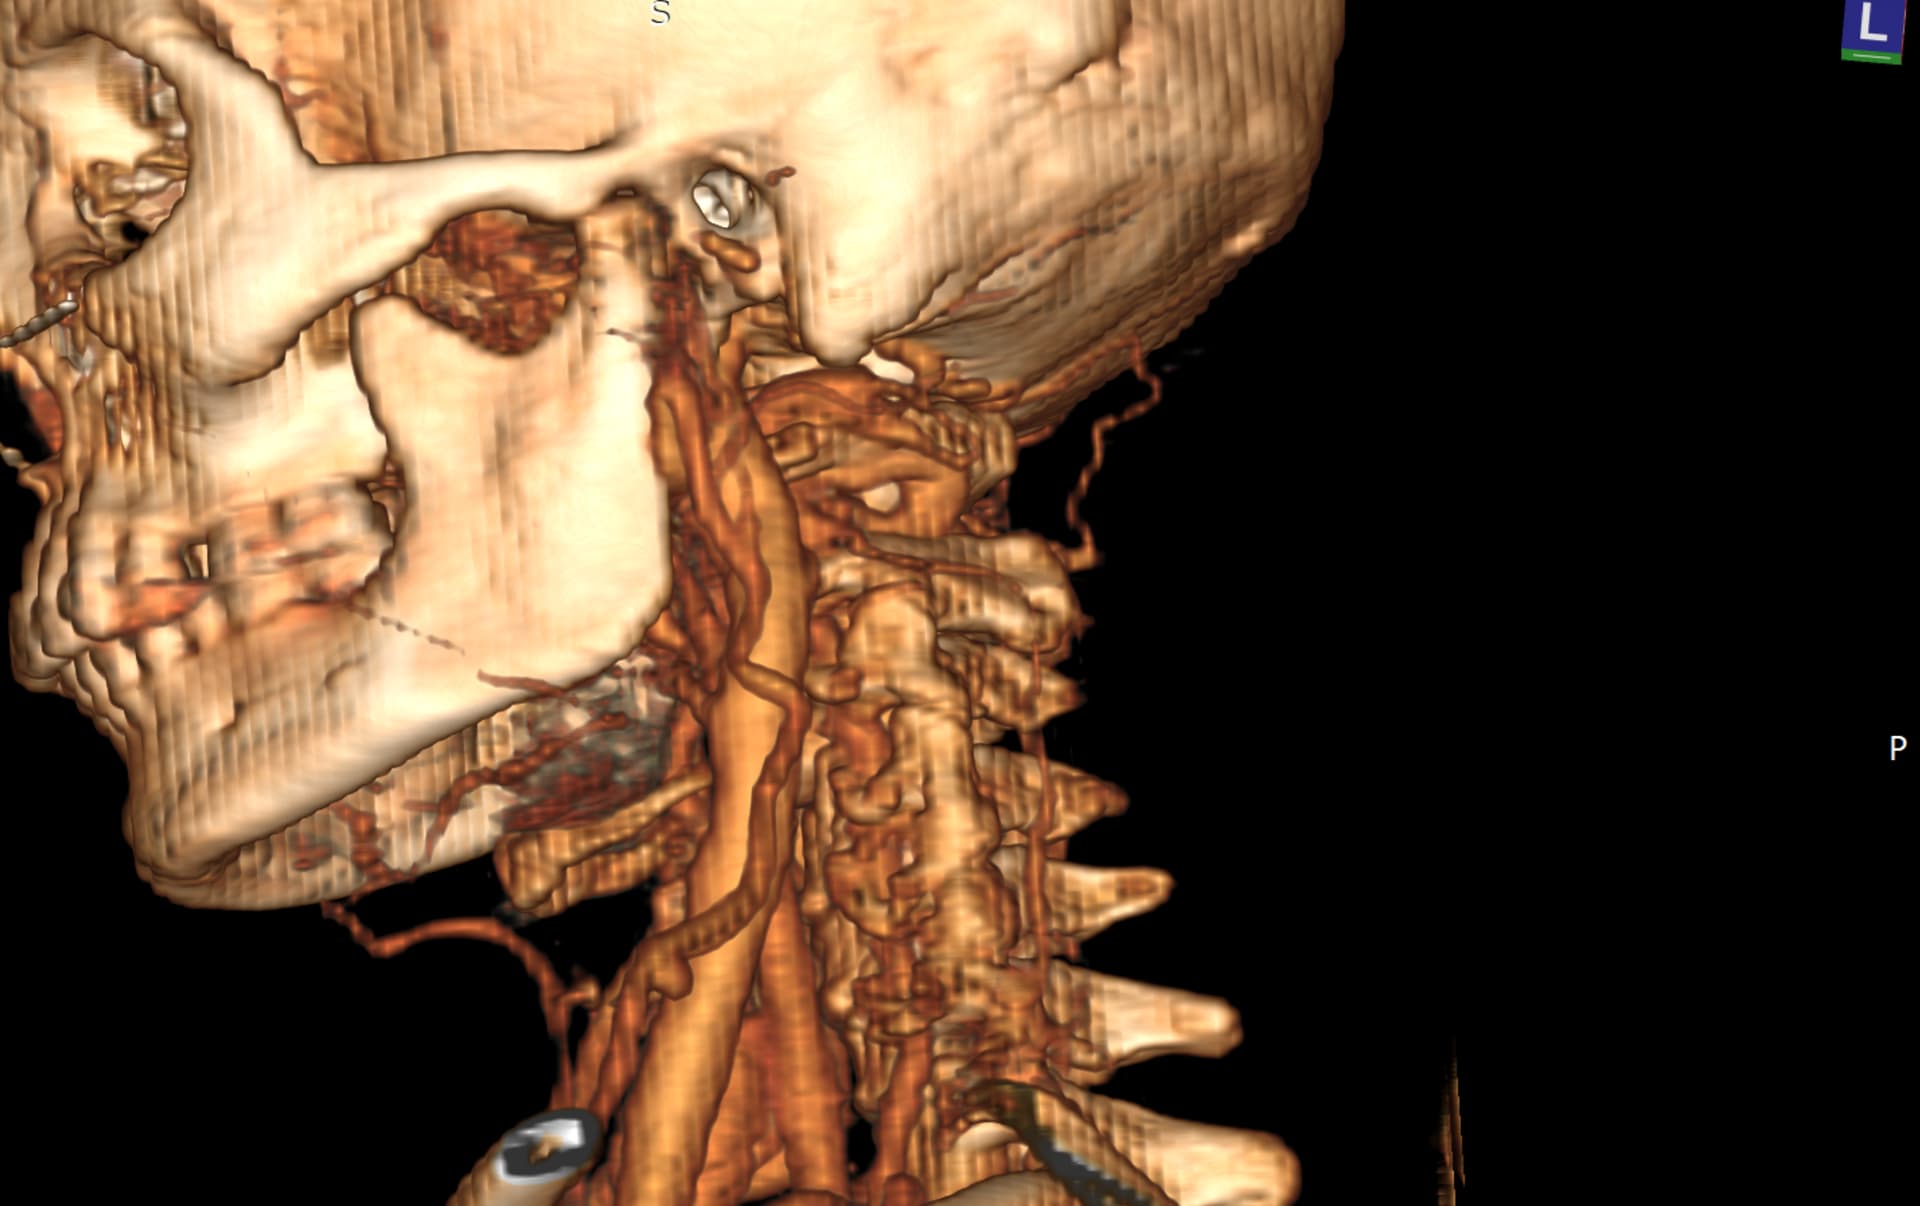

You can actually see the tortuous left ICA run into the left IJV in the 3D model I posted:

@chrEagle I re-downloaded your CT to get better 3D images of the compression in question.

See attached. Hope this helps!